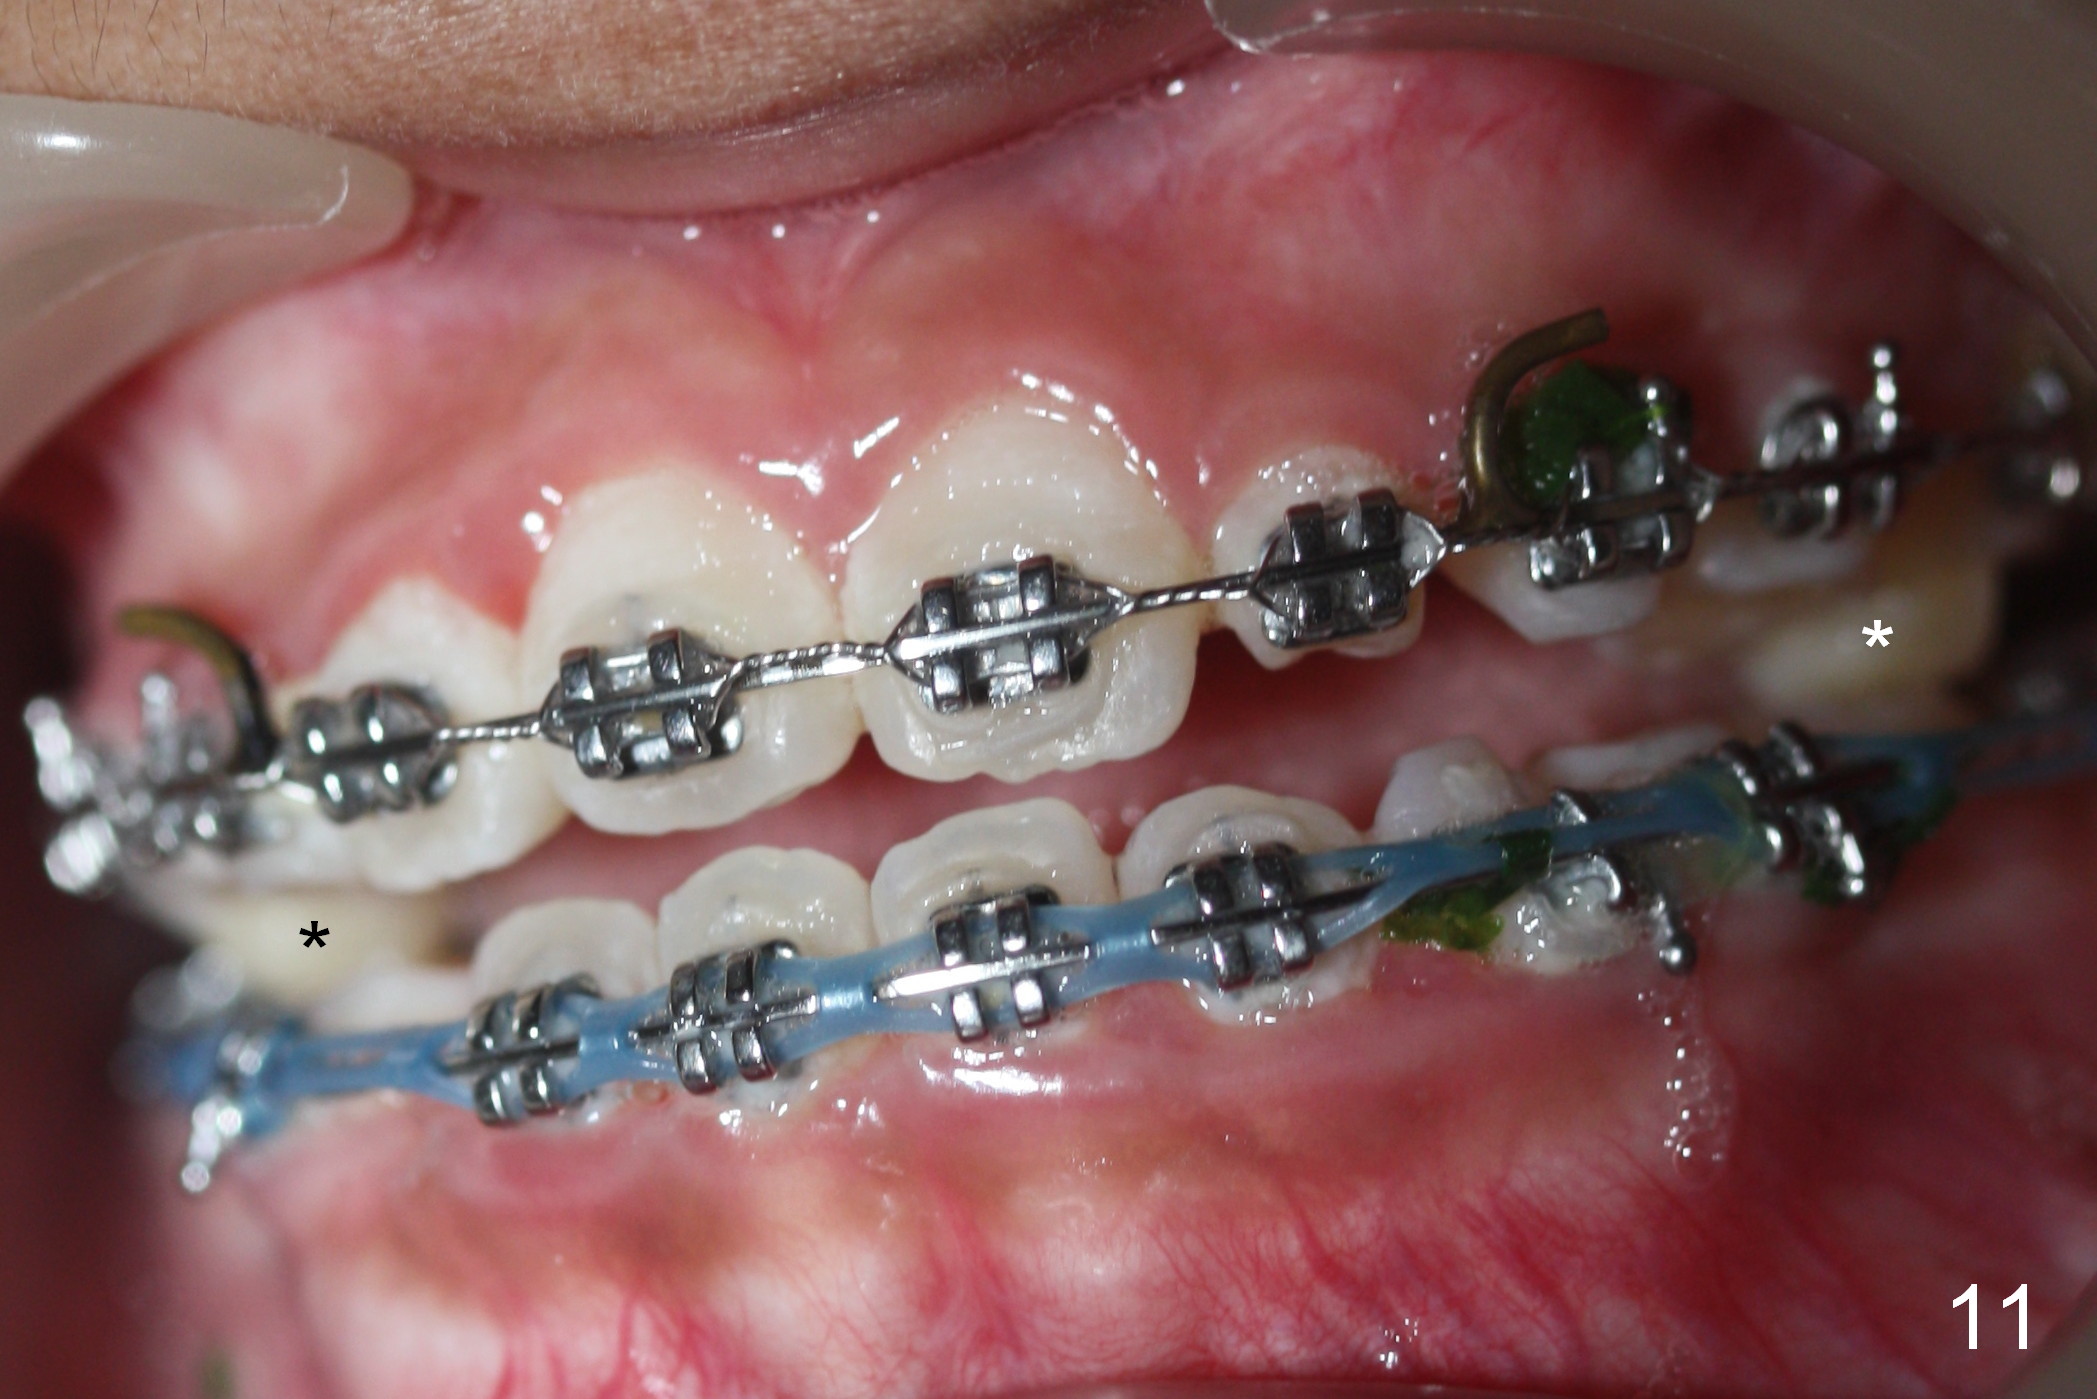

Face bow is placed 11 months post banding. One month later (wear face bow after dinner), the facial profile (Fig.10) and cross bite (Fig.11) improve. Next visit check anterior overjet and canine and molar relationship! Take photos if needed, especially for posterior occlusion. The occlusal composite is reduced in the next few appointments to decrease anterior open bite.